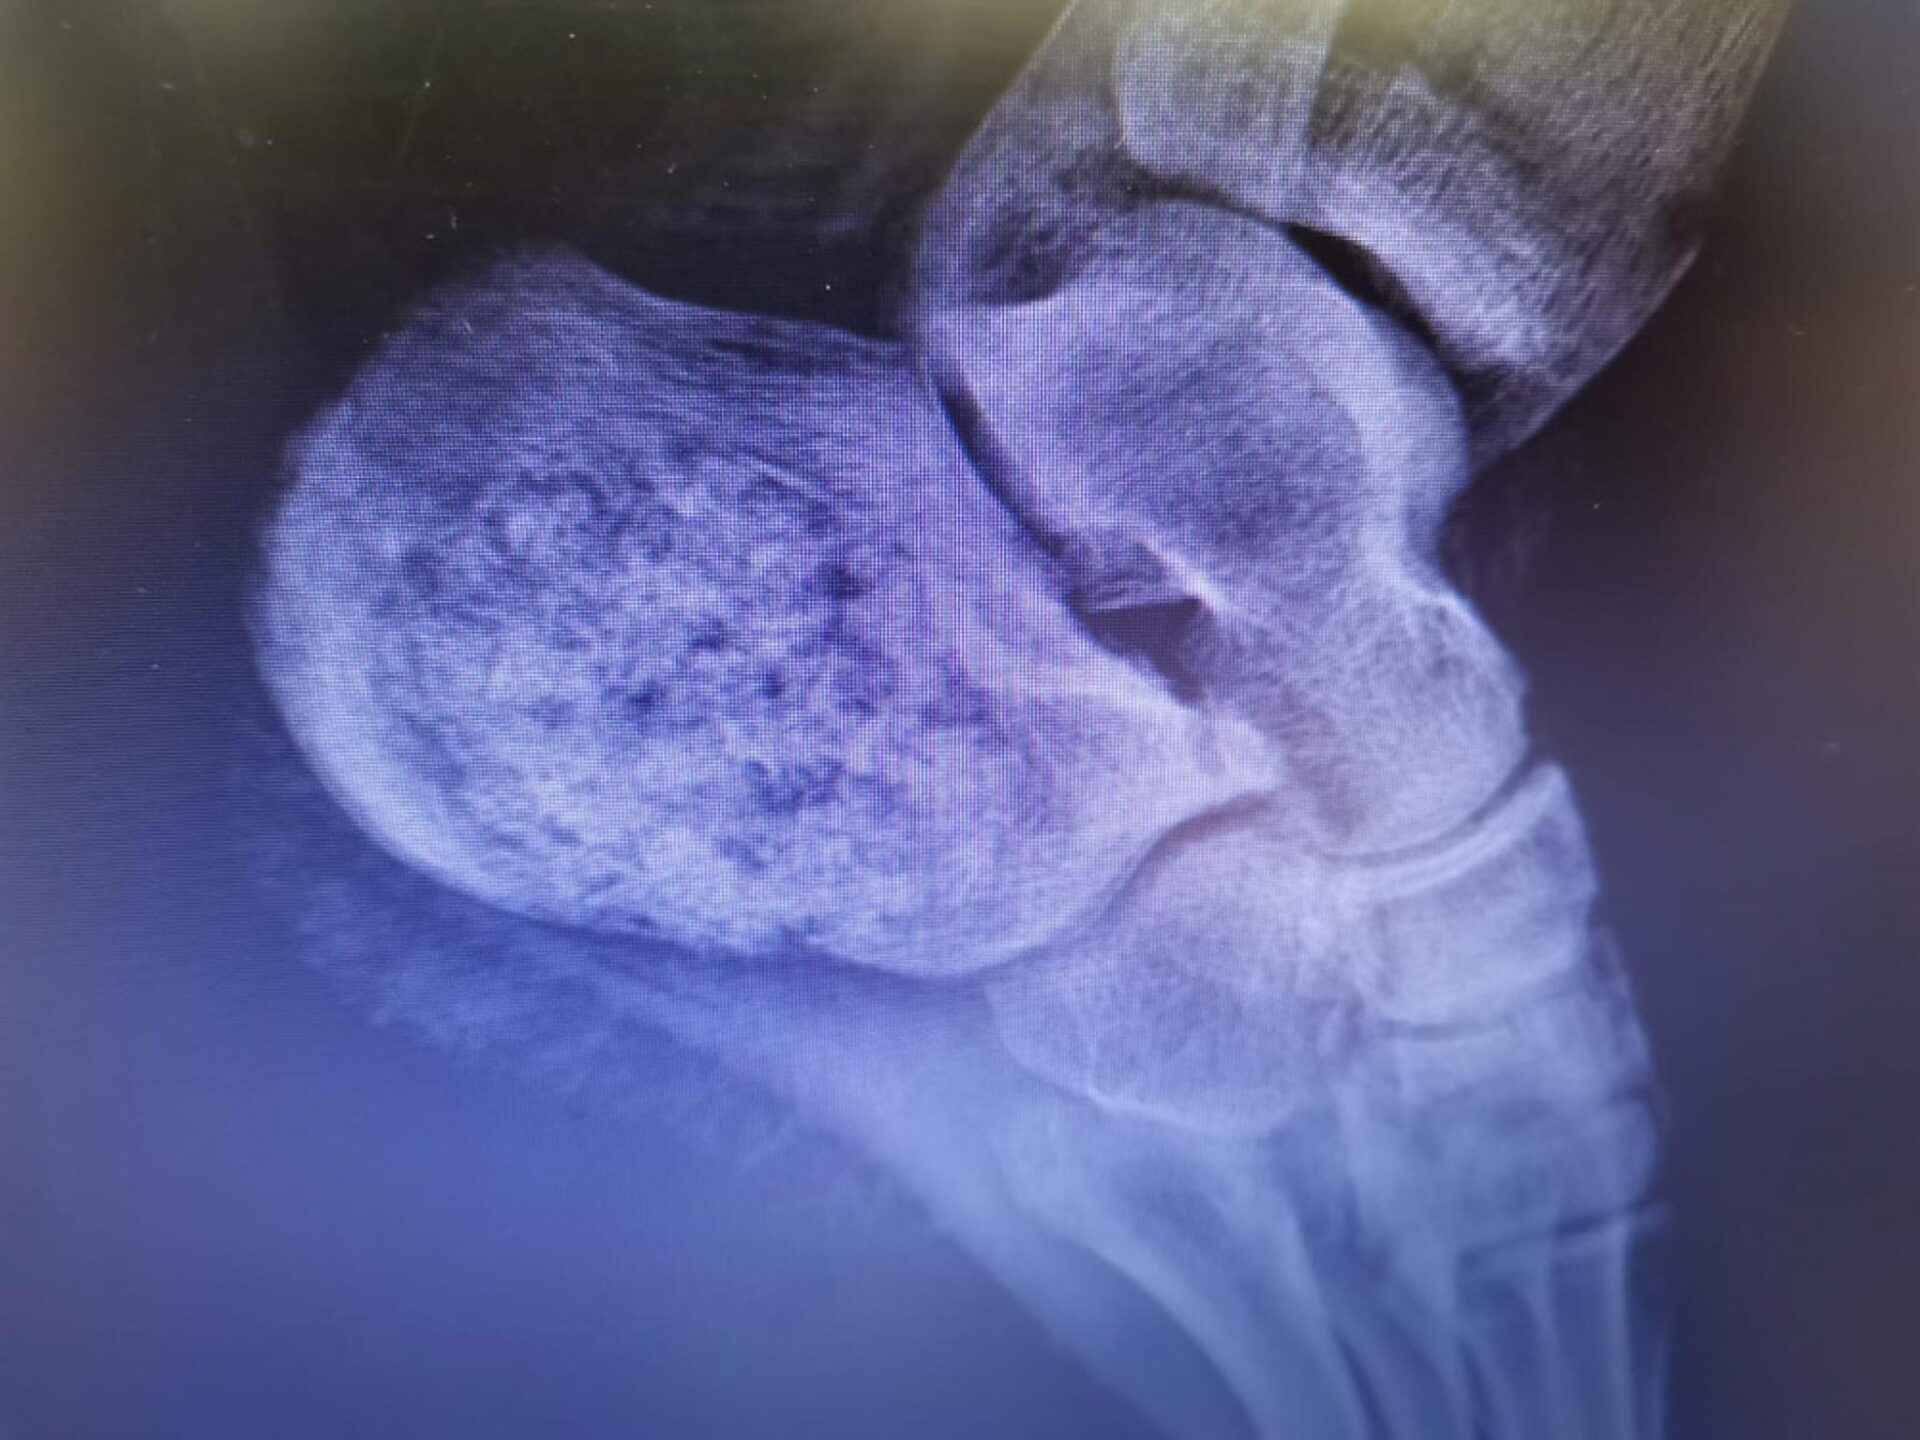

Un caz de tumoră la nivelul unui nerv, extrem de rar întâlnită, a fost diagnosticată și tratată cu succes de medicii de la Spitalul Județean de Urgență „Sf. Ioan cel Nou” Suceava, care a devenit astfel al șaselea spital din lume în care a fost diagnosticată o astfel de formațiune. Purtătorul de cuvânt al spitalului, dr. Dan Teodorovici, a arătat că pacienta în vârstă de 20 de ani a fost diagnosticată, în urmă cu aproximativ o lună, cu o formațiune tumorală numită schwannom sau neurinom, care provoca măcinarea osului la nivelul călcâiului stâng, cuprinzând aproape în totalitate osul calcaneu. Doctorul Răzvan Codrin Bandac, șeful secției Ortopedie a Spitalului de Urgență Suceava, a declarat că acest caz este deosebit deoarece este vorba despre o tumoră extrem de rară, care a produs un grad ridicat de distrugere osoasă. Acest lucru a necesitat reconstrucția osului cu transplant de os uman, cu care a fost corectat defectul rezultat după îndepărtarea țesutului tumoral.

Dr. Bandac a explicat că intervenția chirurgicală a decurs în doi timpi, inițial practicându-se îndepărtarea marginală a tumorii, în urmă cu 3 săptămâni, și efectuarea de către medicii anatomo-patologi, dr. Andreea Botezan și dr. Luminița Miron, a examenului histopatologic. Acest lucru a permis diagnosticarea rapida a unui schwannom intraosos, o tumoră benignă a nervului periferic, excepțional localizată la acest nivel.

„În literatura de specialitate sunt citate numai 5 cazuri de acest fel”, a subliniat dr. Bandac.

Tumora